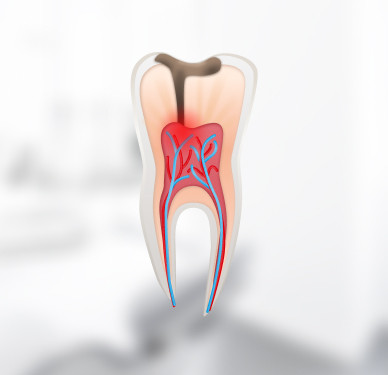

Кариес – самое распространённое заболевание полости рта. Без своевременного лечения оно приводит к пульпиту. Основные симптомы кариеса — потемнение эмали и появление углублений, повышенная чувствительность зубов к горячему и холодному, неприятный запах изо рта. Игнорирование этих симптомов может стать причиной потери зуба или его дорогостоящего лечения.

В клинике «Новая Орбита» вы получите квалифицированную помощь в лечение любых заболеваний полости рта: кариеса, пульпита, периодонтита и других. Проводим лечение без бормашины и с минимальным травматизмом. Проверенная европейская анестезия подбирается строго с учётом индивидуальных показателей пациента.

Мы делаем всё возможное, чтобы сохранить поражённый зуб, избежать необходимости дальнейшего протезирования или имплантации.